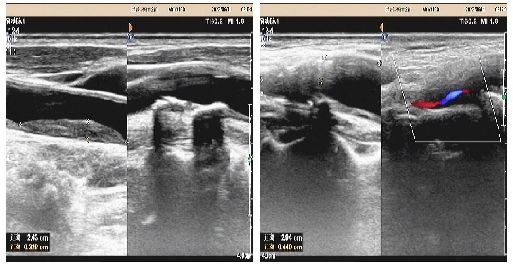

02、**男士,49岁

于2023年6月19日在邯郸仁泰北区体检,膀胱输尿管彩超检查提示:膀胱出口处等回声团,大小约2.1*1.0cm,CDFI:其内及周边可见血流信号。诊断: 膀胱出口处等回声团。立即通知客户家属带客户去专科医院进一步检查,2023年7月25日跟踪回访,客户家属告知,已在邯郸市中心医院东区检查,检查结果和我体检中心相同,并在中心医院东区做病理确诊为膀胱癌,属于早期,客户家属表示幸亏做体检,早期发现了病变,感谢仁泰体检。

03、**男士,67岁

于2023年6月14日在邯郸仁泰东区体检,颈动脉彩超检查提示:双侧颈总动脉内中膜局部增厚,较厚处约0.13cm。左侧颈动脉内可见多个斑块,较大的位于颈动脉中段后壁,大小约2.6cm*0.3cm的低回声斑,右侧颈动脉内可见多个斑块,较大的位于颈总动脉分叉处前壁至颈内起始处前壁,大小约2.9cm*0.44cm混合回声斑,造成颈内起始处管腔狭窄,狭窄率约90%,CDFI:斑块处血流充盈缺损。立即通知客户到专科医院进一步检查。2023年7月13日跟踪回访,客户告知,已在邯郸某三甲医院住院准备支架治疗。